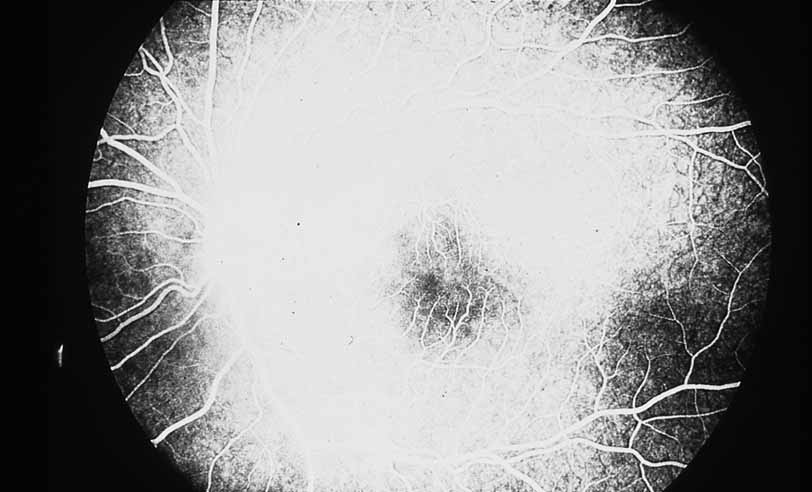

MACULAR INVOLVEMENT

One of the most useful applications of fluorescein angiography in infections and inflammations of the posterior segment is the delineation and quantization of cystoid macular edema. Although it is generally possible to ascertain the presence or absence of gross cystoid macular edema in eyes with clear media, this is often not the case in eyes with intraocular inflammation. The presence of intraocular inflammation, such as the vitreous cells accompanying pars planitis31–33 or sarcoidosis, 34–40 may prevent clear viewing of the macula. The tell-tale hyperfluorescence seen in the normally hypofluorescent macula after dye injection is an important indicator. The presence of cystoid macular edema by angiography may lead the clinician to take a more aggressive posture in the treatment of these diseases, especially in younger patients in whom some uncertainty exists regarding the relative contribution of the media opacity versus the macular function to the reduced vision (see Figs. 6 and 7).

Fig. 6 Presumed ocular histoplasmosis. This patient developed decreased vision with mild vitritis. Color photograph shows a hazy view of the central macula.

Fig. 7 Presumed ocular histoplasmosis. Fluorescein angiogram of Figure 6 demonstrates cystoid macular edema as the cause of this patient's decreased vision.

Once a treatment regimen has been instituted, the follow-up fluorescein angiogram can serve as a marker for treatment response in addition to other clinical variables, including visual acuity and severity of intraocular inflammation (see Fig. 8).

Fig. 8 Presumed ocular histoplasmosis. Repeat fluorescein angiogram from Figure 7 shows complete resolution of cystoid macular edema after intravitreal injection of triamcinolone–acetamide.